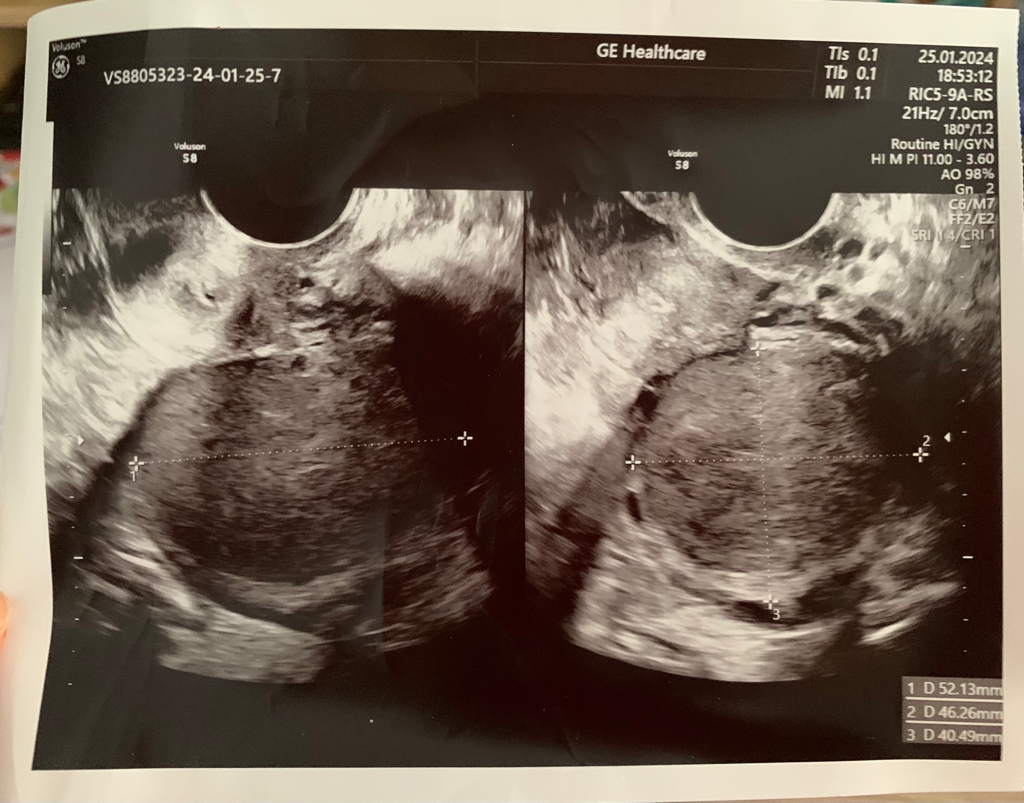

안녕하세요. 현재 해외에 거주중인데요. 생리를 16일동안 해서 병원 갔더니 자궁에 혹이 있다고 하더라구요. 영어로 상담받아서 자궁 근종인지 뭔지 정확히는 모르겠어요ㅠ 아래에 초음파 사진 첨부했습니다.

• 1번 째 사진

근종의 크기가 5cm 정도 되는 상태이니 근종이 꽤 커진 상태입니다. 출혈이 멈추지 않는다면 추가적인 진료를 요하는 상황이므로 3주 뒤 산부인과 진료를 다시 받아보시기 바랍니다.